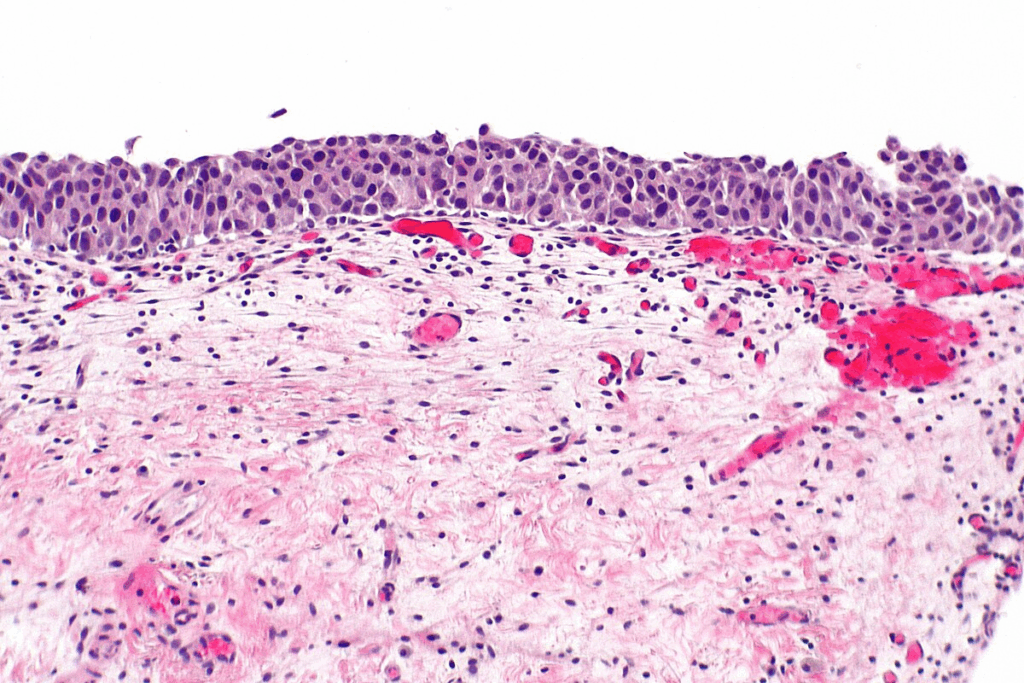

Microscopic Appearance Under Pathological Examination

Under a microscope, cancer in situ cells look different from normal cells and invasive cancer cells. The key features include:

1. Atypical cells with hyperchromatic nuclei

2. Loss of normal cellular polarity

3. Increased mitotic activity

Pathologists look at tissue samples to find these signs, which are vital for diagnosing cancer in situ.